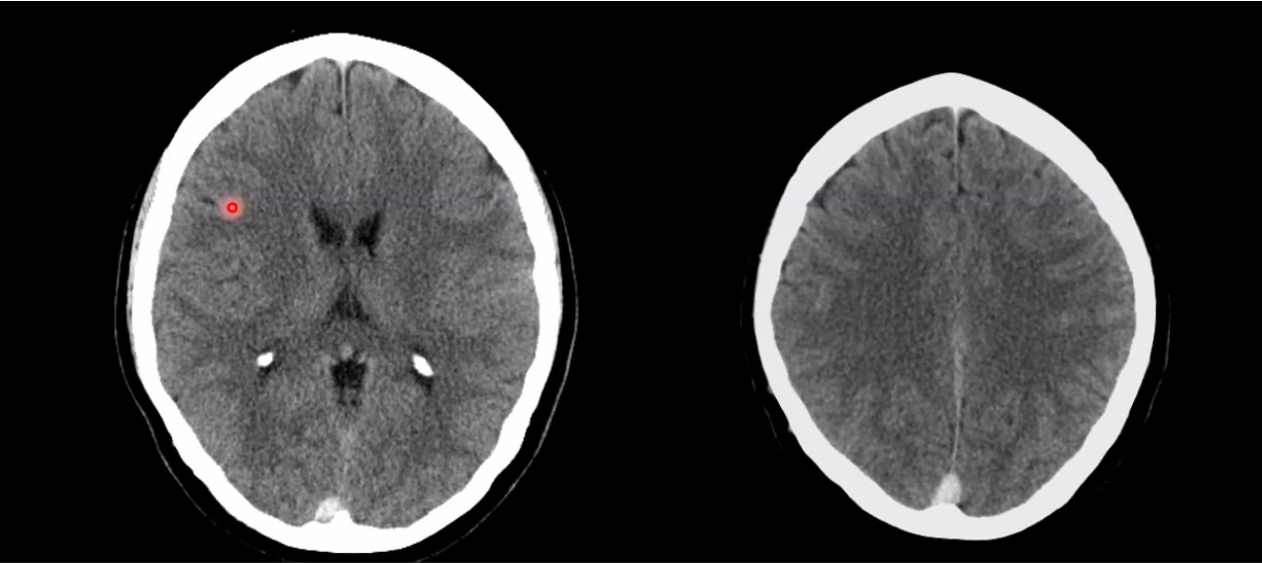

what are each of these entities (they are different cases)

cav mal in the conus medullaris

chocolate covered popcorn